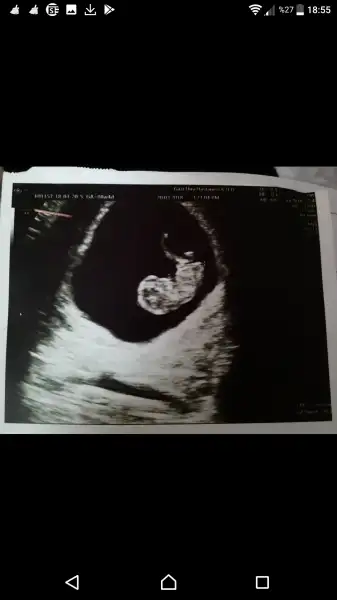

Selam kızlar bugün doktora gittim sat a göre 8+4 ama ultrason da 9+3 çıktı miniğim. Kızlar çok erken ama cinsiyet tahminlerinizi bekliyorum

Eki Görüntüle 2126263 Selam kızlar bugün doktora gittim sat a göre 8+4 ama ultrason da 9+3 çıktı miniğim. Kızlar çok erken ama cinsiyet tahminlerinizi bekliyorum